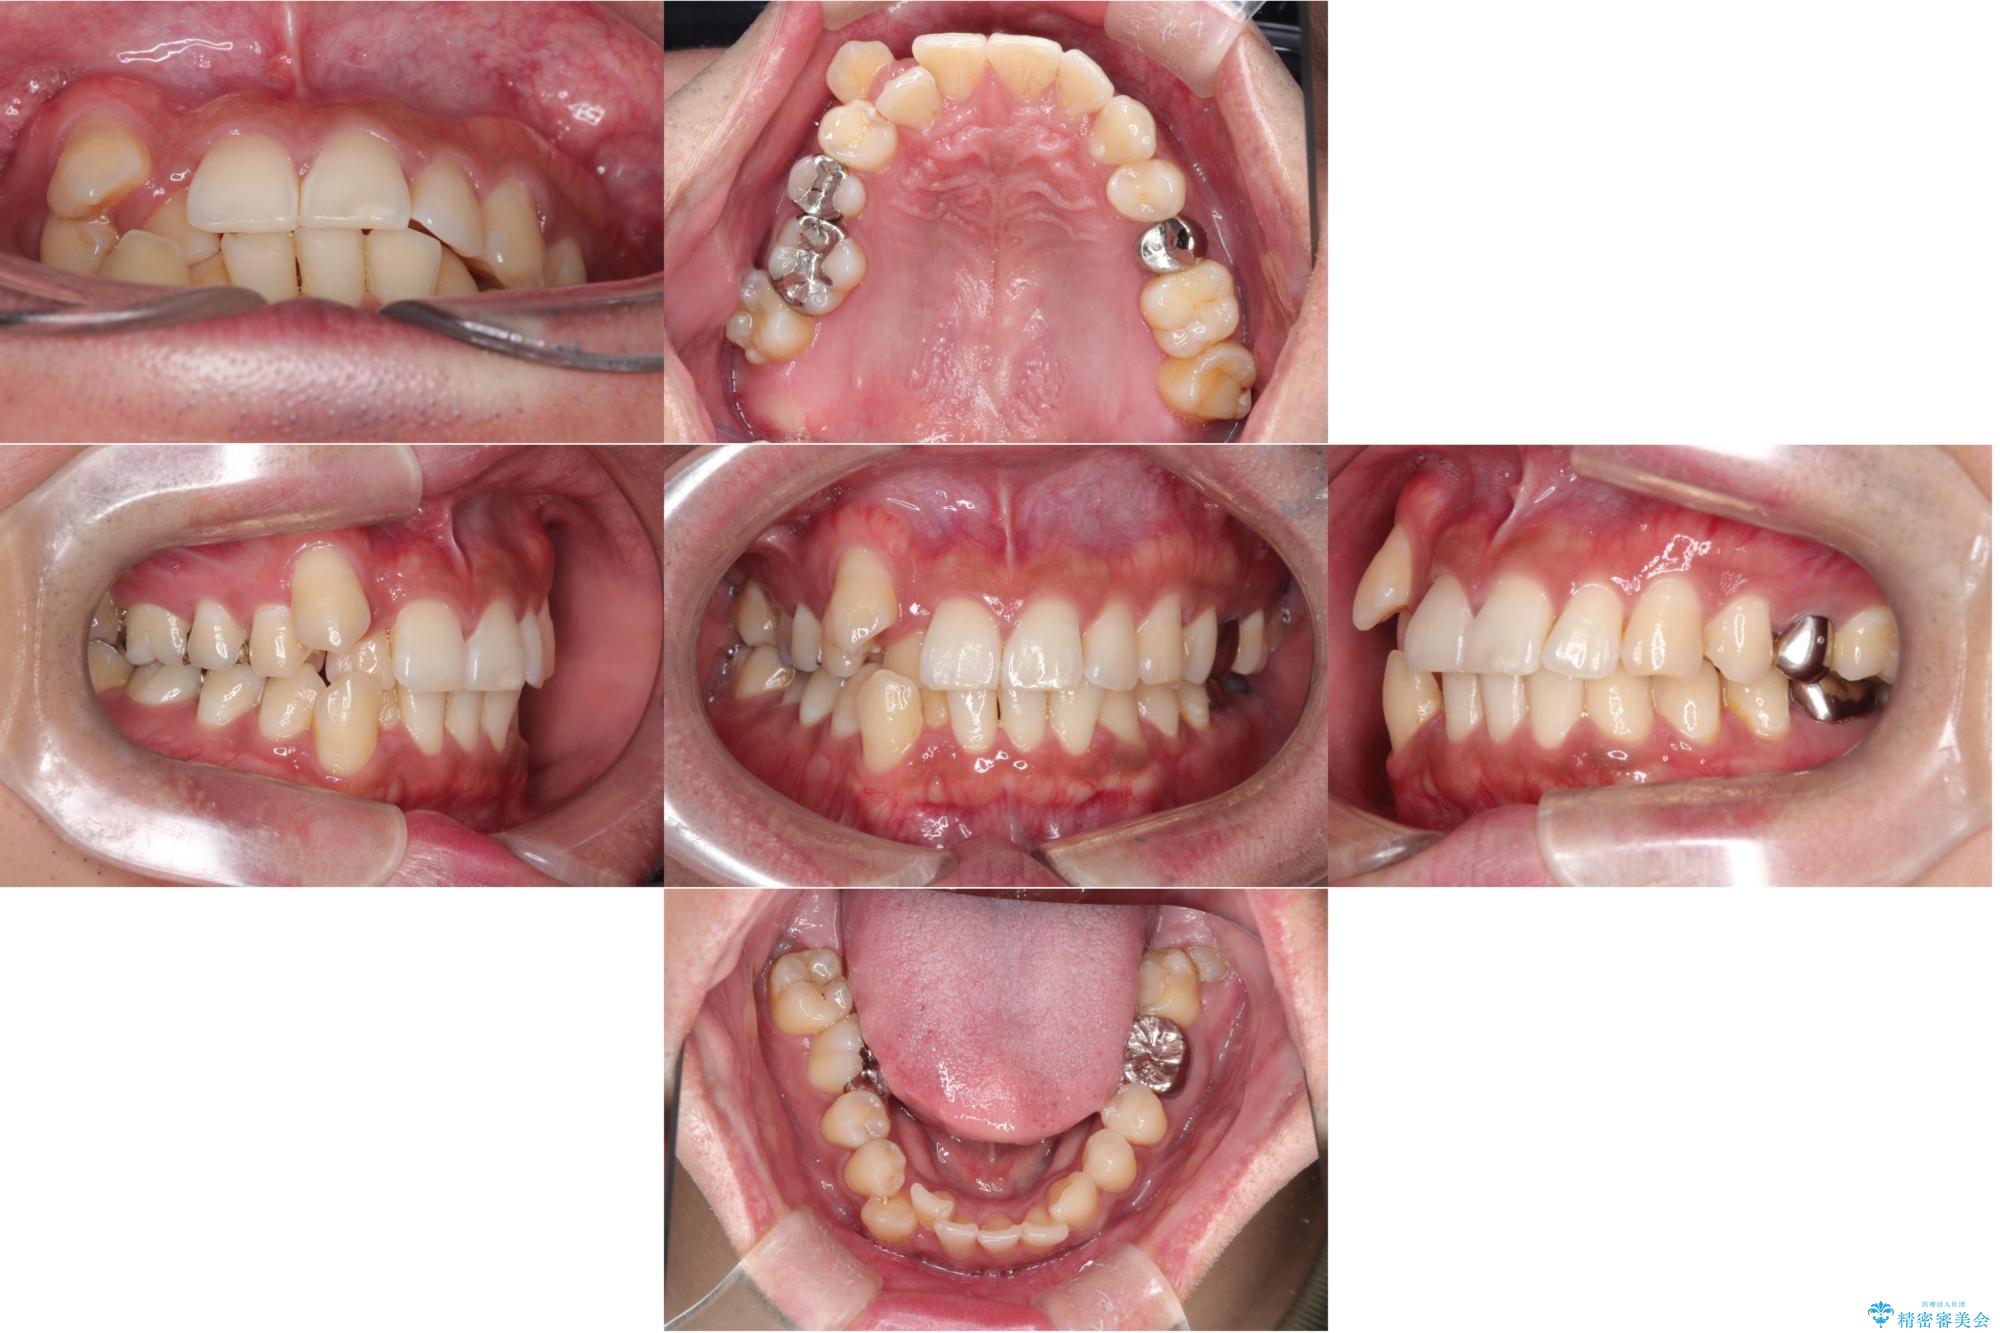

【ワイヤー矯正】八重歯と下の歯の凸凹を治したい

- 主訴:右上の八重歯と、下の歯の凸凹を治したい

上顎右側第一小臼歯と下顎右側第一小臼歯を抜歯しワイヤー矯正を行いました。

右側2級、左側1関係だったため、右側上下第一小臼歯を抜歯し、ワイヤー矯正を行いました。